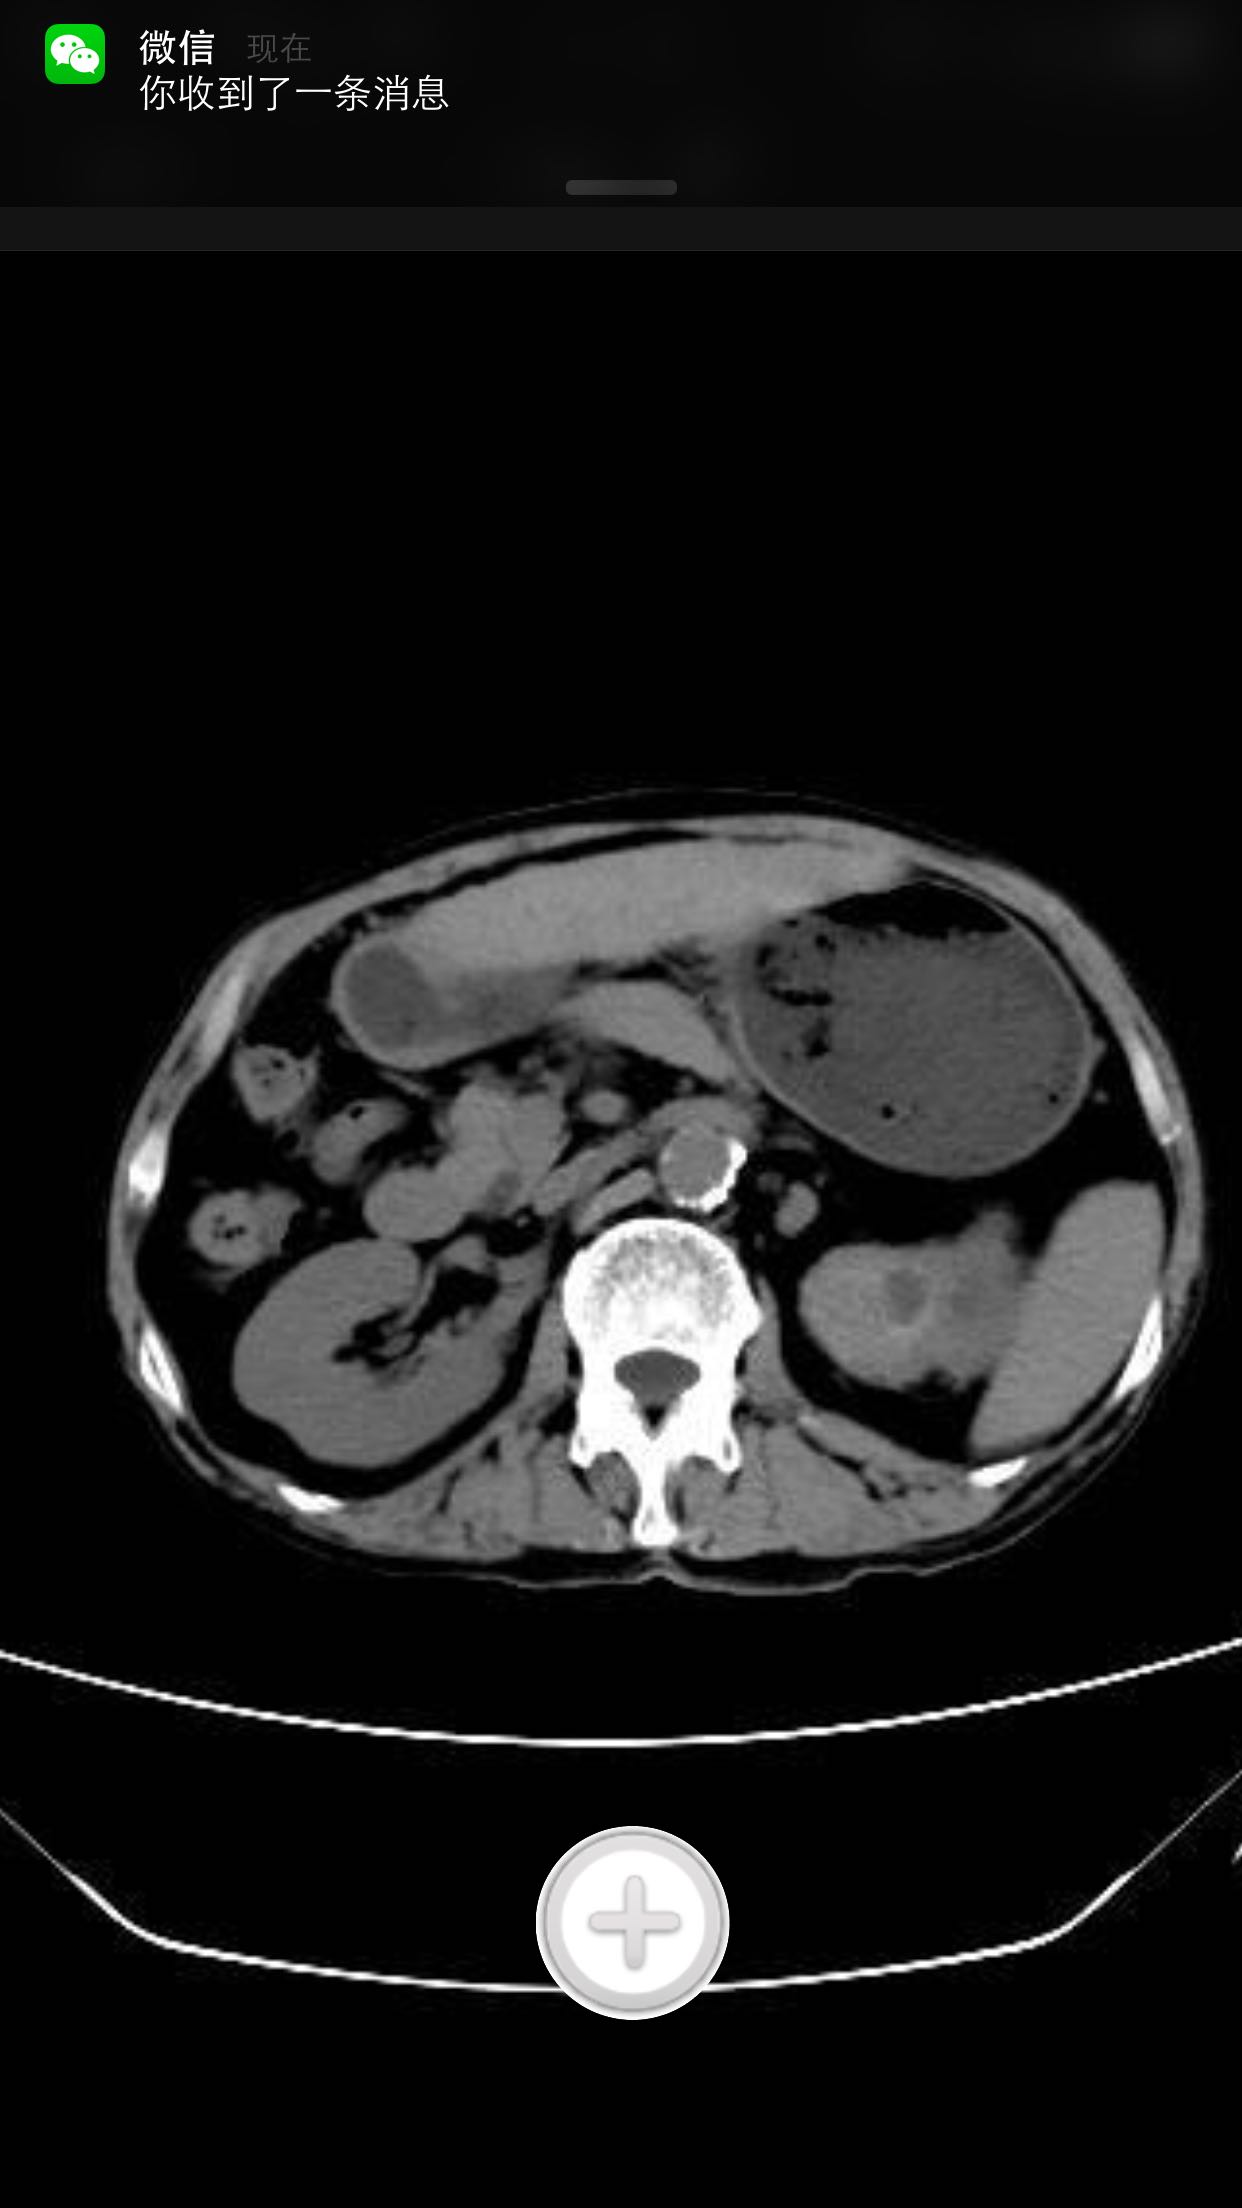

排尿困难,尿潴留入院。诊为前列腺增生症,拟行手术治疗。完善术前检查,泌尿系CT检查发现左肾占位,左肾结石并左肾重度积水,左肾萎缩等。既往患者肺结核病史,服药控制半年余。

查体:腹平软,无压痛及反跳痛,无肾区叩痛,肛诊前列腺明显增大,中央沟消失,无硬结,无压痛。术前强化CT提示左肾癌。

术前诊断:1、左肾癌2、左肾结石3、左肾积水4、左肾萎缩5、前列腺增生6、肺结核 入院后完善检查,拟行TURP,因发现左肾癌,改为先行肾手术。患者左肾癌,同时左肾结石,肾萎缩,决定行根治性肾切除,拟腹腔镜下手术,患者家属不同意,改开放手术,全麻下行根治性左肾切除。术后剖开标本如下图,肿瘤位于肾上极,中间黑色为结石。